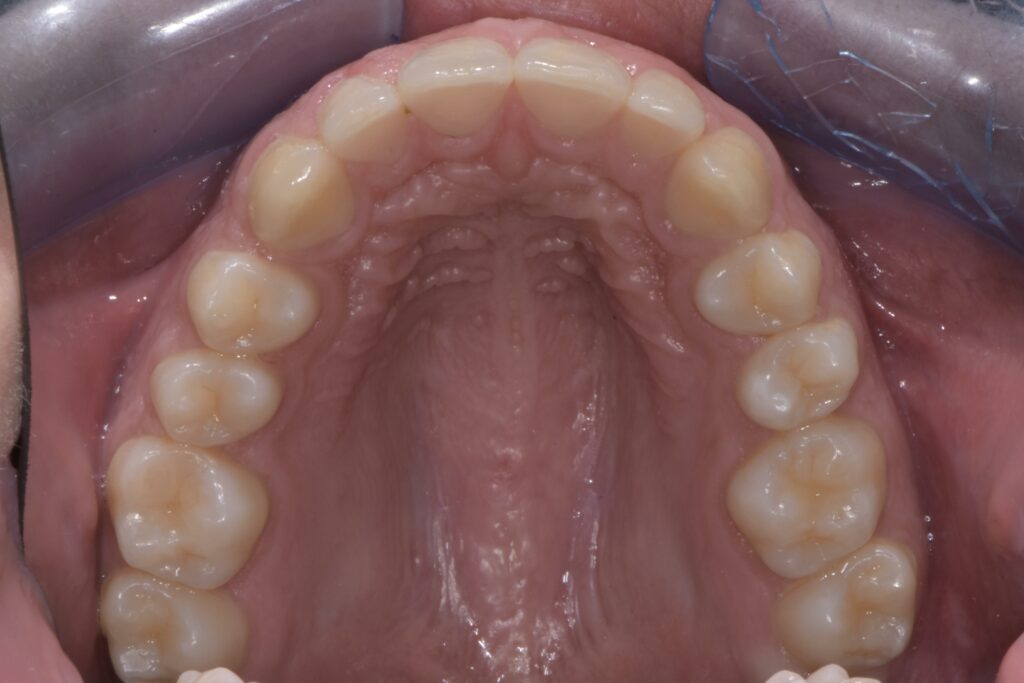

Prima della sigillatura:

- Superficie dentale con solchi e fossette evidenti, aree ad alto rischio di accumulo batterico.

- Maggiore vulnerabilità alle carie, specialmente nei molari e premolari permanenti.